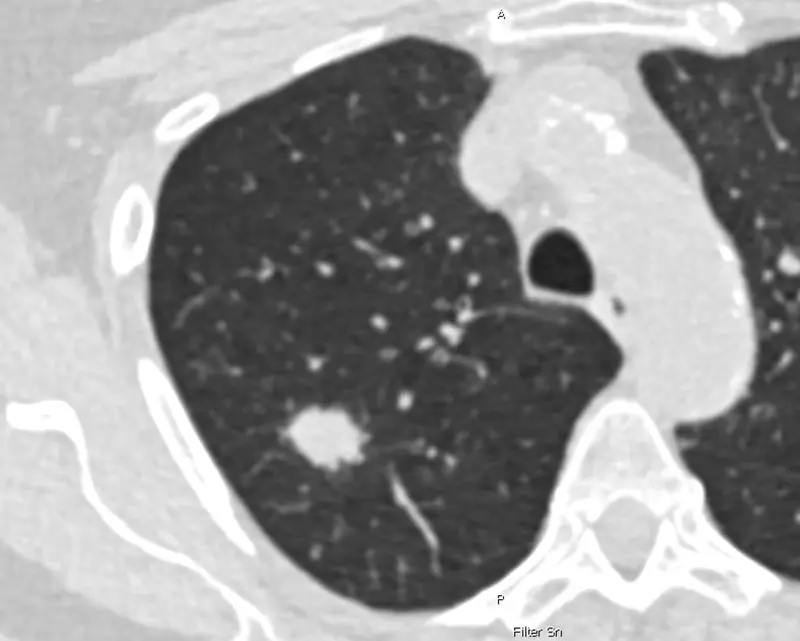

Jährlich werden in Deutschland bei etwa 57.000 Personen Lungenkrebs diagnostiziert, oft mit tödlichem Ausgang, da die Erkrankung meist zu spät entdeckt wird. Das geplante Programm soll bei Personen mit hohem Risiko mittels Computertomografie (CT) verdächtige Lungenveränderungen überprüfen. Bisher vorgesehen sind Teilnehmende zwischen 50 und 75 Jahren, die mindestens 25 Jahre stark geraucht haben und entweder noch rauchen oder vor weniger als zehn Jahren aufgehört haben, wobei der Tabakkonsum rechnerisch mindestens 15 Packungsjahre ergeben muss.

Die Daten der HANSE-Studie deuten darauf hin, dass diese Kriterien einige Personen mit hohem Risiko übersehen, die vom Programm profitieren könnten. Durch Berücksichtigung weiterer Faktoren ließen sich knapp 20 Prozent mehr Lungenkrebsfälle entdecken, wie der Leiter der Studie, Prof. Jens Vogel-Claussen, erklärt. Er ist Direktor der Klinik für Radiologie an der Charité und hat die Studie an der MHH initiiert.

Bei rund 4.200 aktiven oder ehemaligen Rauchenden, die nach PLCOm2012 gescreent wurden, wurden 108 Lungenkrebsfälle gefunden, 19,4 Prozent mehr als in der NELSON-Gruppe mit rund 3.900 Personen und 85 Fällen. Mit dem erweiterten Score müssten etwa sechs Prozent mehr Personen gescreent werden, aber das Screening werde effizienter, da weniger CT-Untersuchungen pro Diagnose nötig seien, wie Prof. Martin Reck, Chefarzt des Onkologischen Schwerpunkts an der LungenClinic Grosshansdorf, feststellt.